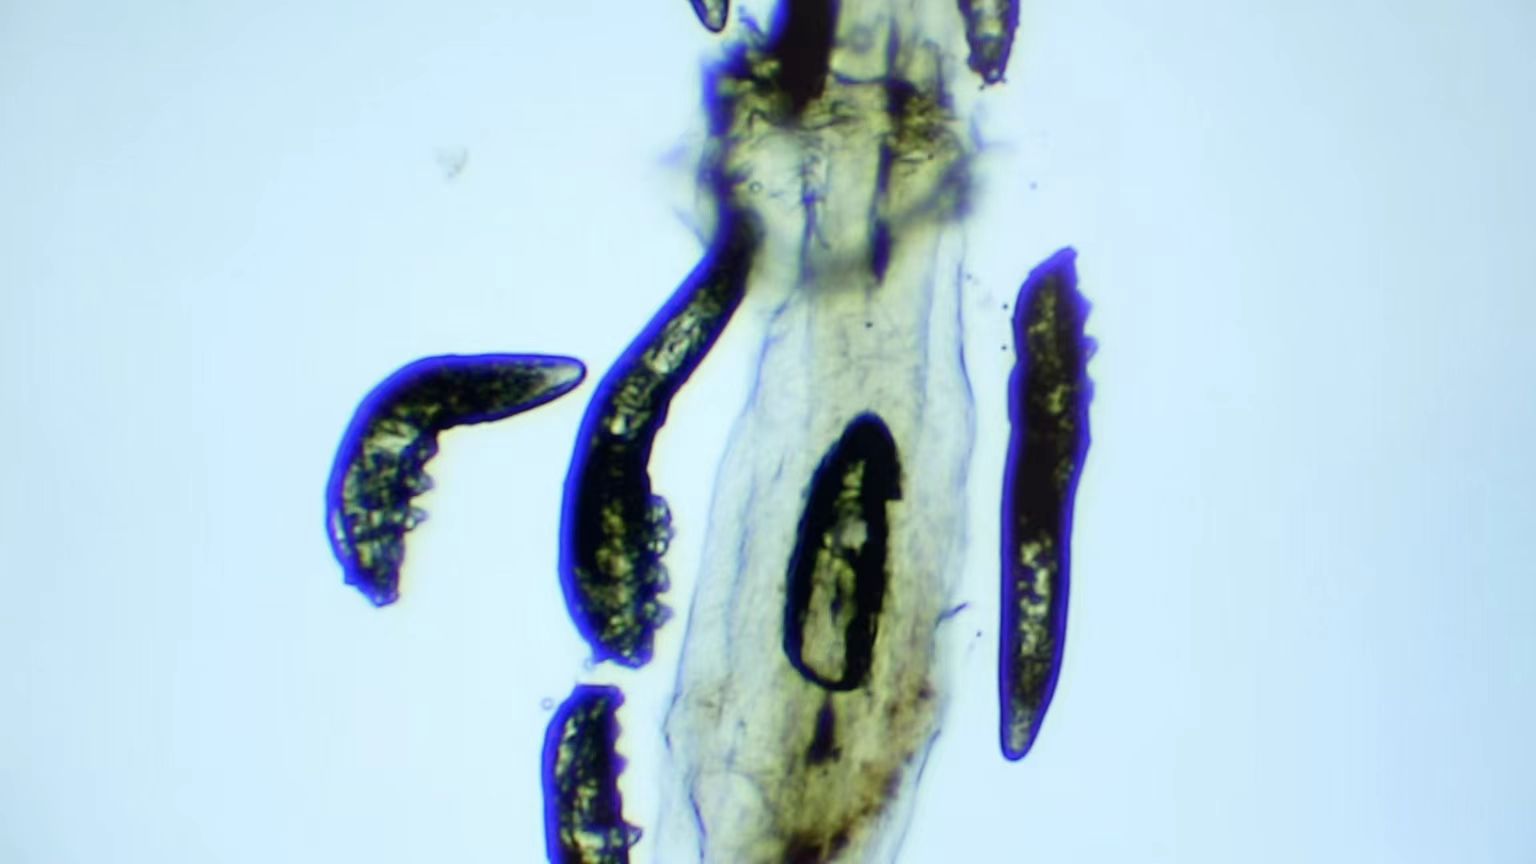

我院開設(shè)有干眼特色門診,可通過在顯微鏡下檢查拔取的睫毛,有效判斷是否存在過量蠕形螨。